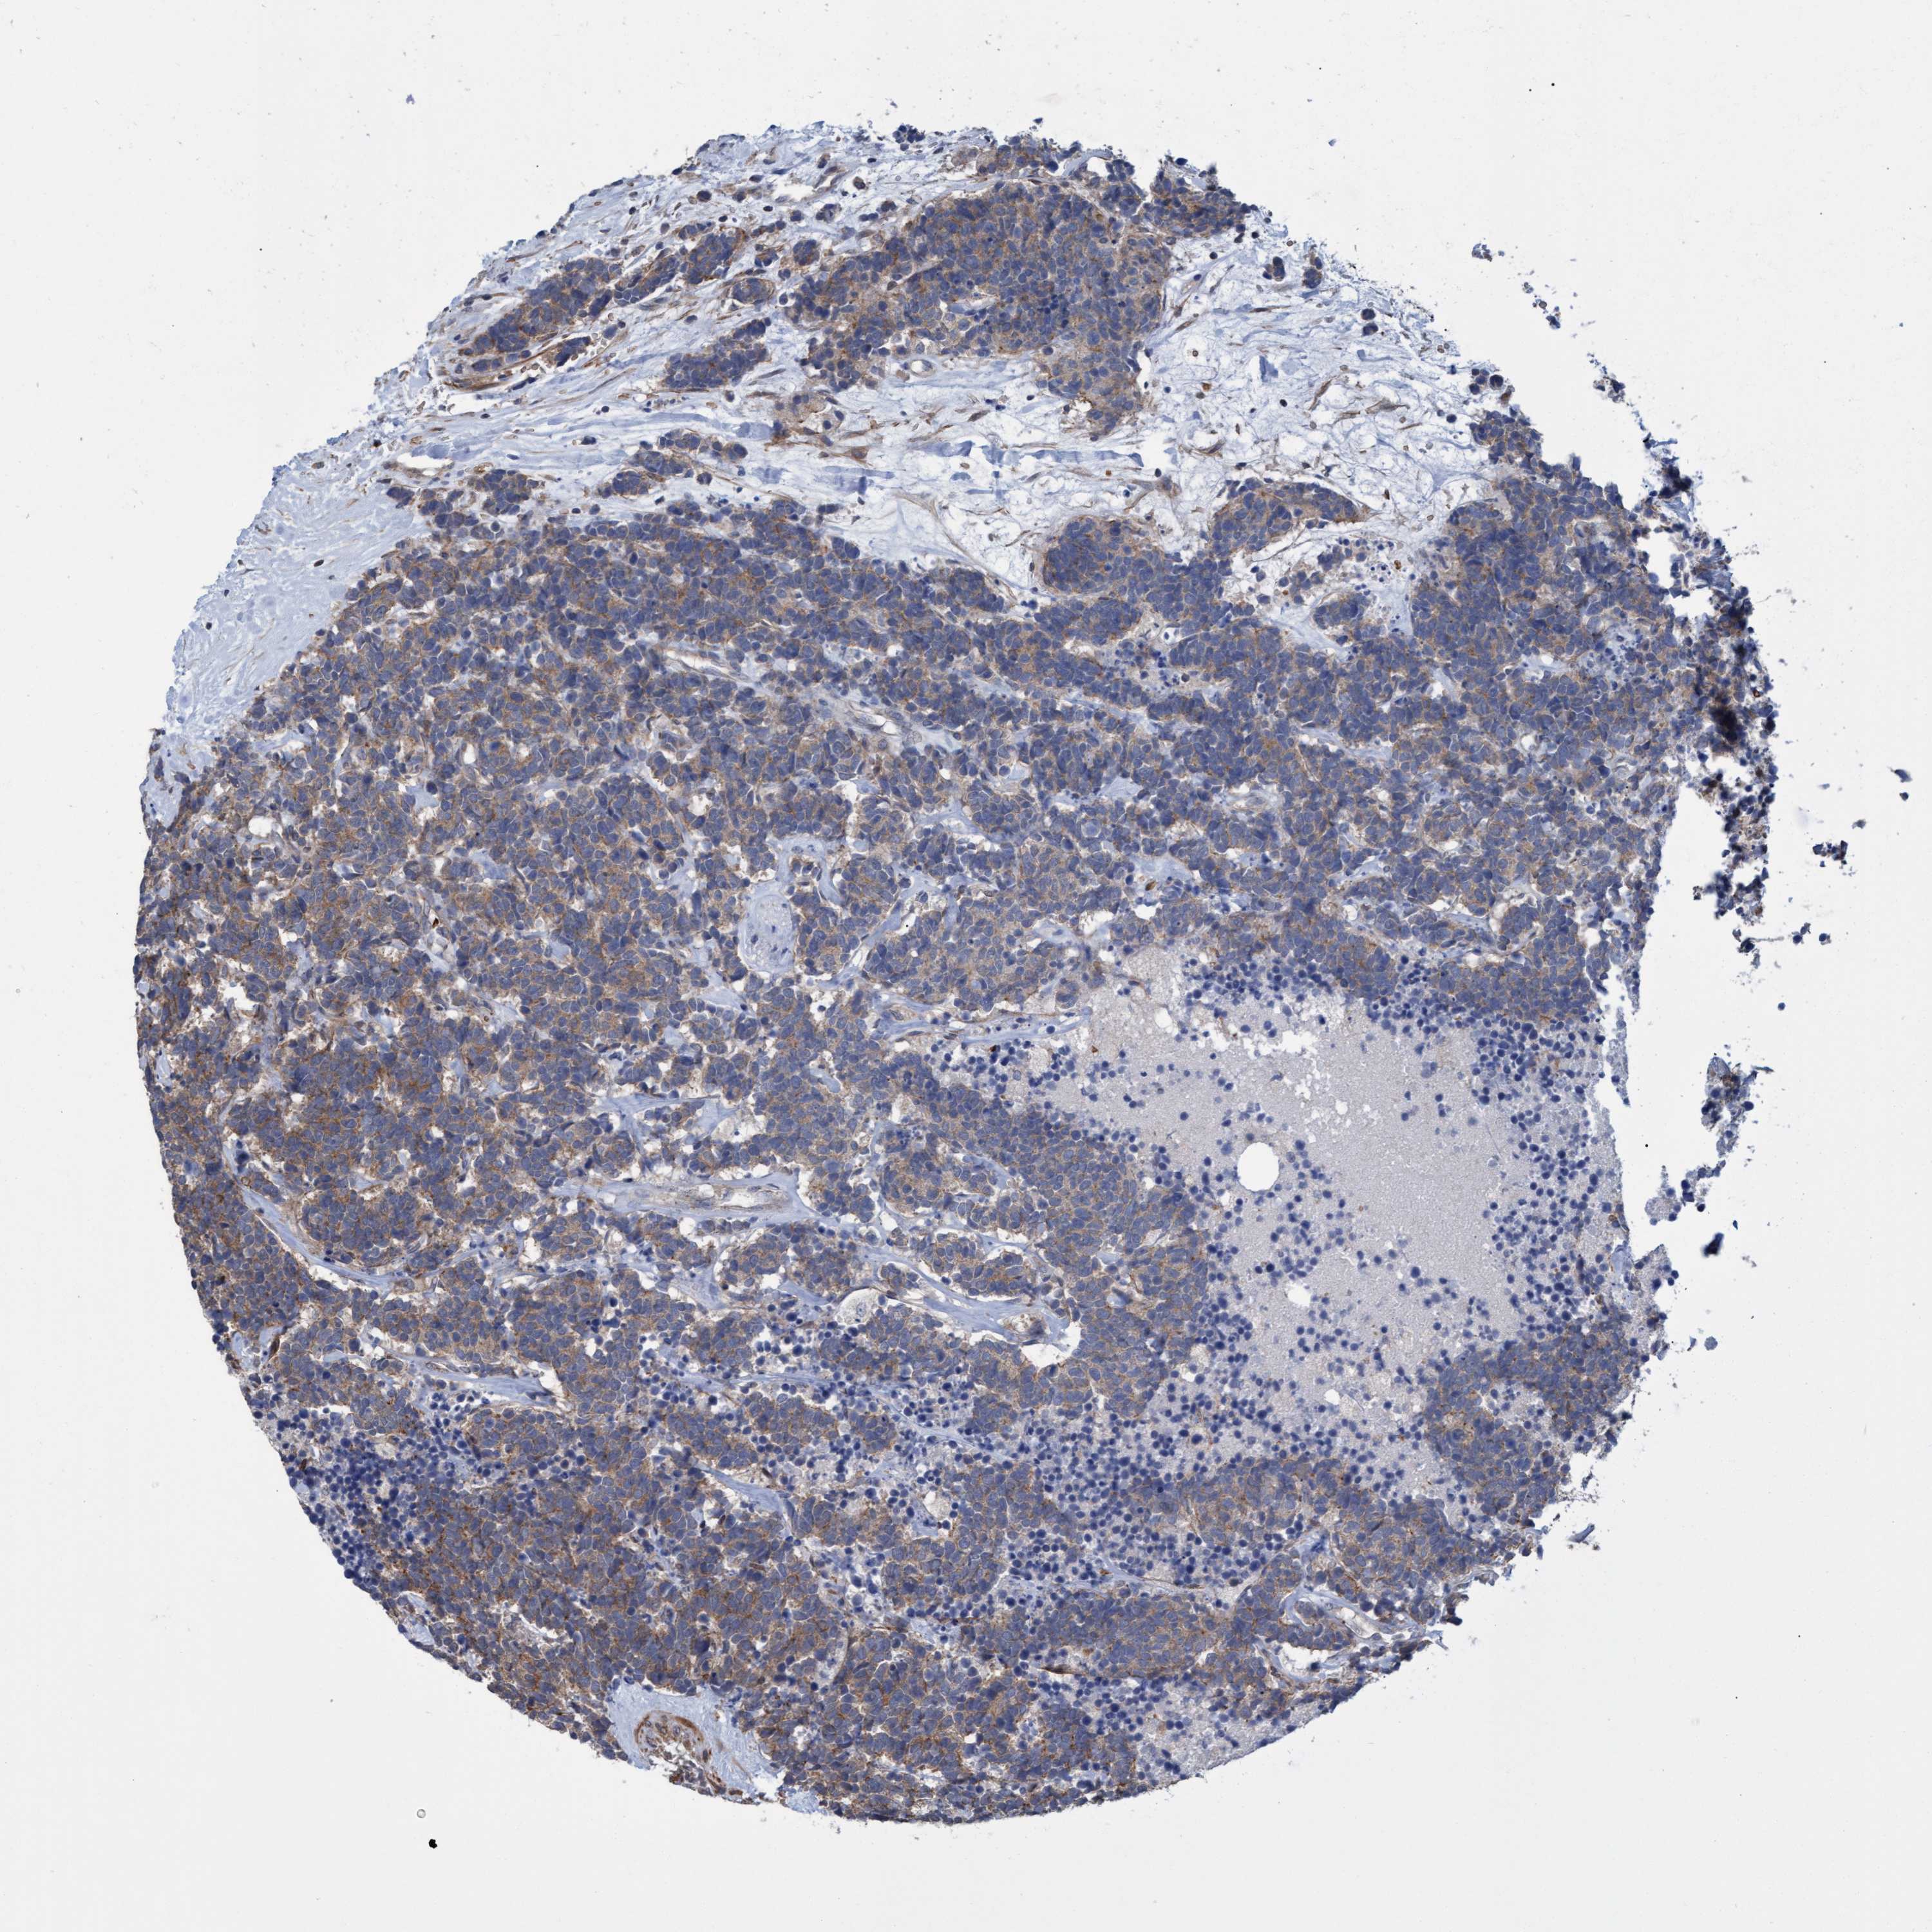

NAA15